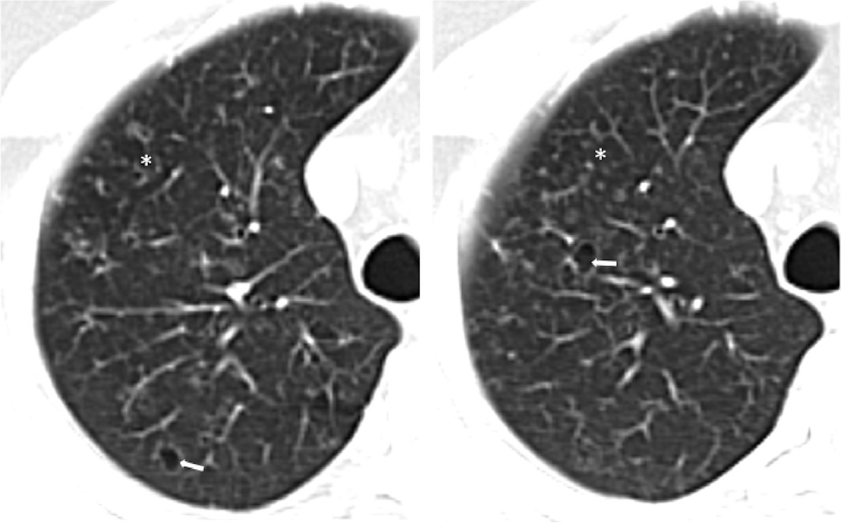

BHD的囊往往会出现比较巨大的泡、有些不规则,靠近下肺和纵膈的情况比较多。

下图也是一个BHD病例,表现为肺部囊性病变+肾脏肿瘤+皮肤异常,提示我们一定鉴别TSC和BHD、要注意肺外表现。

图:BHD,肾透明细胞癌

最后,了解一下Birt-Hogg-Dube综合征(BHD)。肺部囊性病变出现于90%的BHD患者(常具有气胸和/或家族史),是一种常染色体显性遗传疾病,多有家族史,通过FLCN基因突变能够明确诊断,也可伴有皮肤和肾脏肿瘤,需要仔细查看。